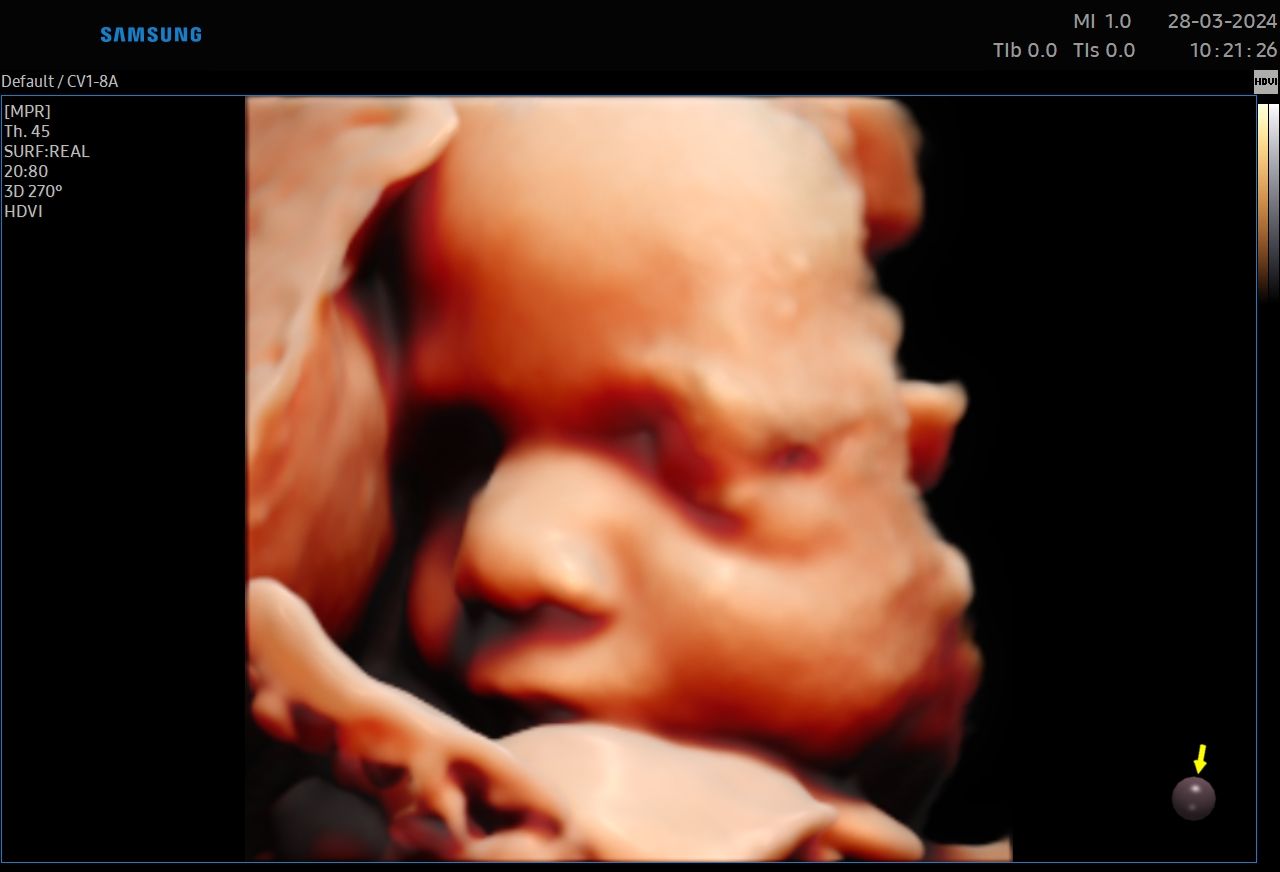

:-) Jestem lekarzem specjalistą w zakresie ginekologii i położnictwa , w ramach prowadzonej praktyki ginekologicznej staram się świadczyć kompleksowe porady lekarskie najwyższym poziomie ,w oparciu o najwyższe standardy jak i przy pomocy najnowszego sprzętu medycznego. W trakcie pracy zawodowej uzyskałem kolejno tytuły specjalisty I stopnia , a później specjalisty II stopnia , a także uzyskałem dodatkowe uprawnienia

CERTYFIKAT BADAŃ PRENATALNYCH POLSKIEGO TOWARZYSTWA GINEKOLOGÓW I POŁOŻNIKÓW

CERTYFIKAT BADAŃ PRENATALNYCH FMF ( FETAL MEDICINE FOUNDATION - LONDYN )

W ramach praktyki wykonuję pełen zakres badań ultrasonograficznych w zakresie ginekologii jak i położnictwa wraz z badaniami prenatalnymi , badaniami ultrasonograficznymi piersi .

Zdjęcia i filmy